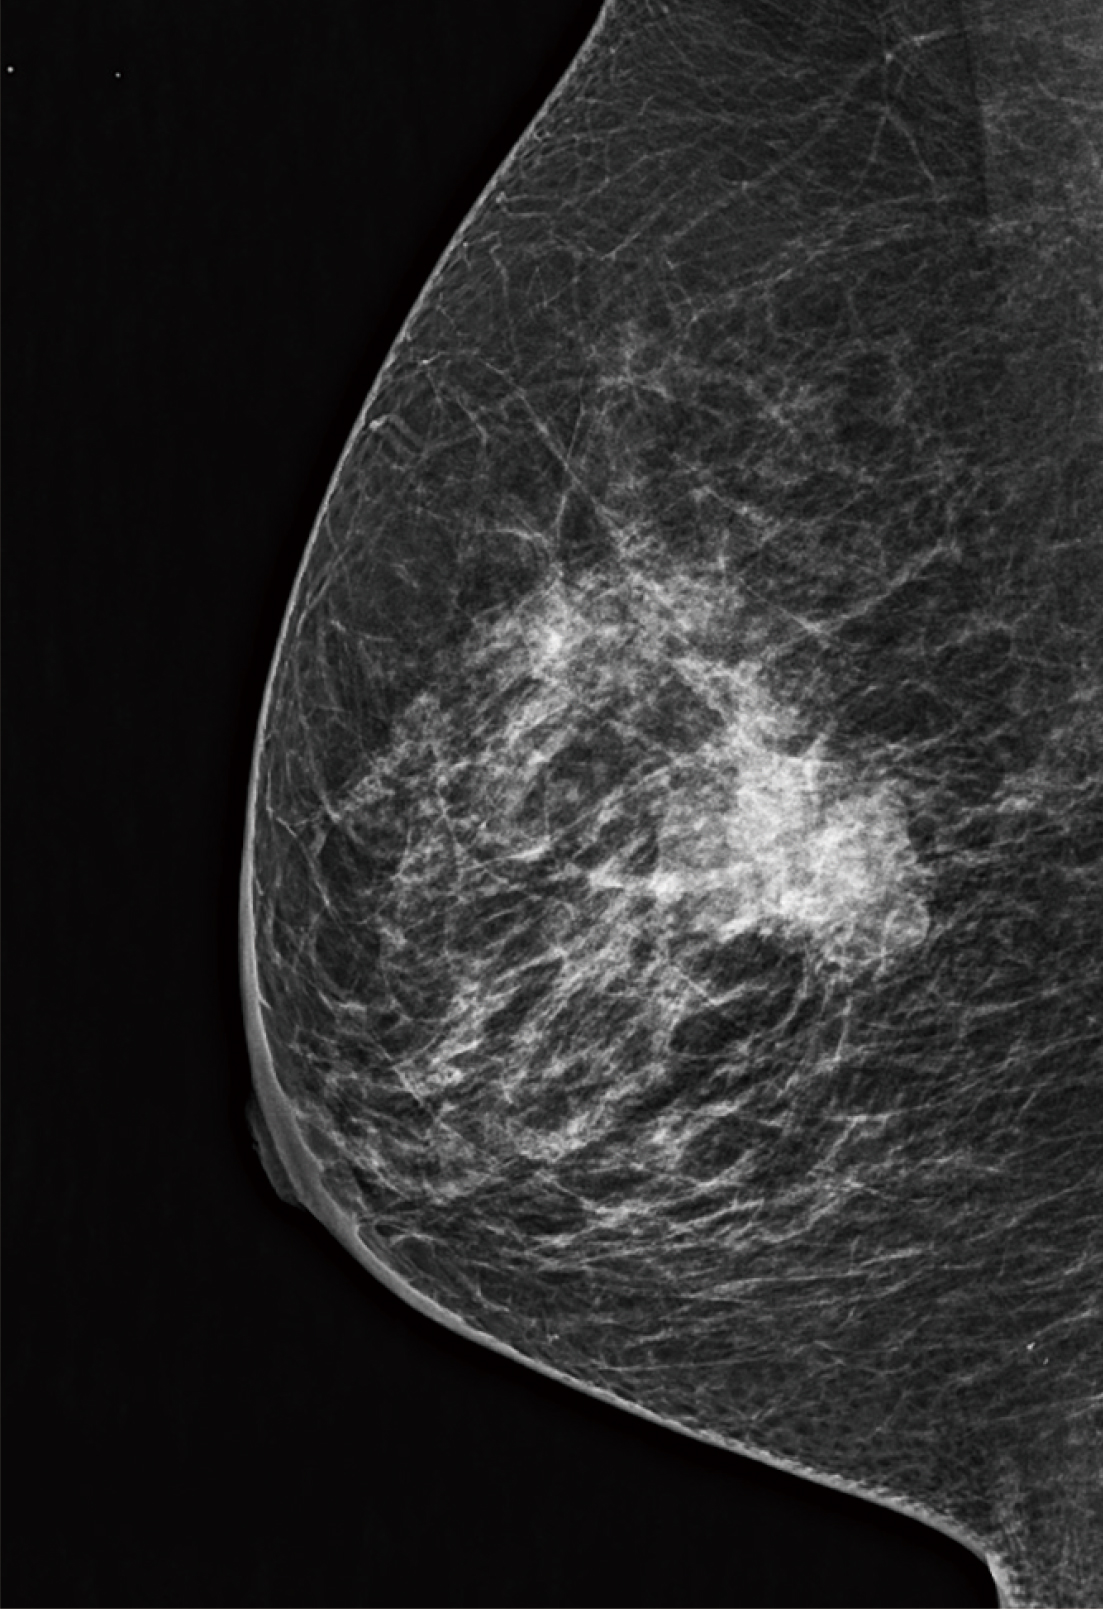

A tecnologia Image-based Spectrum Conversion*1 (ISC) pode ser usada para ajustar o contraste em uma imagem. A ISC analisa imagens para compensar variações no contraste devido à densidade das glândulas mamárias, à quantidade de gordura e ao espectro de raios X. A ISC visa garantir que as imagens exibam contraste adequado mesmo com o uso de um feixe de raios X de baixa dose e alta energia. Essa tecnologia permite que locais que anteriormente exploravam o contraste superior de um alvo de molibdênio percebam as vantagens de dose oferecidas pelo uso de tungstênio sem a necessidade de comprometer o contraste da imagem.

O Dynamic Visualization II (DYN II) exibe a densidade consistente e apropriada dos tecidos glandular e adiposo em cada tipo de mama, melhorando o contraste em mamas espessas e mamas densas. Além disso, ele fornece alto contraste sem saturação na região da mama, de modo que os locais possam definir o parâmetro de alto contraste.